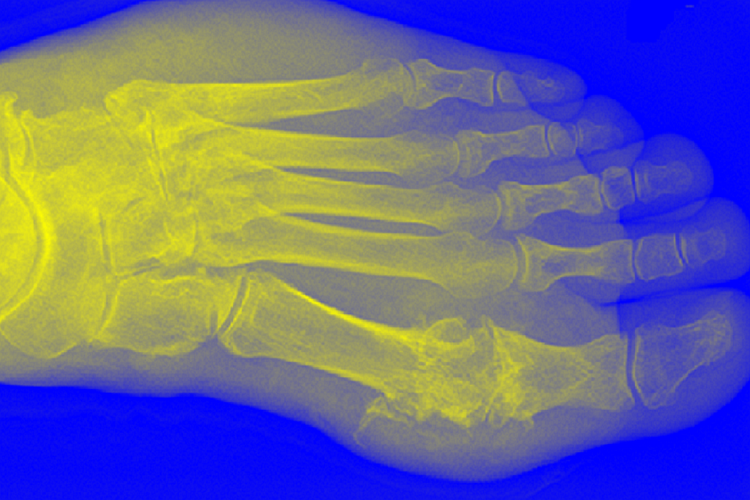

The potential benefit of BHA in treating hyperuricemia and gout has been borne out in preclinical models. TLR4 has be demonstrated to be essential for the mouse gout model induced by urate monohydrate injection into joints. Thus the researchers chose this model as a first test for in vivo activity of BHA. In this model, a single 10 µg or 50 µg injection of BHA was given into joints of mice concomitantly with the monosodium urate. These treatments were compared to a current standard clinical treatment, colchicine, which was given prior to inducing the gout as well as after. In this model (Figure 1.) BHA significantly reduced inflammation-induced swelling to control levels (controls received saline injection) and BHA reduced swelling more quickly and to a larger extent than colchicine. Concurrent with these benefits significant beneficial changes were seen in serums levels of Il-1β, IL-8, Il-10, MCP-1 and IFNγ.